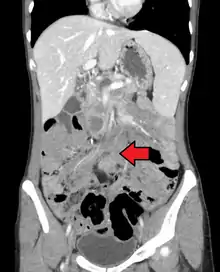

Desmoid tumor as seen on CT scan

SpecialtyOncology, surgery, radiology